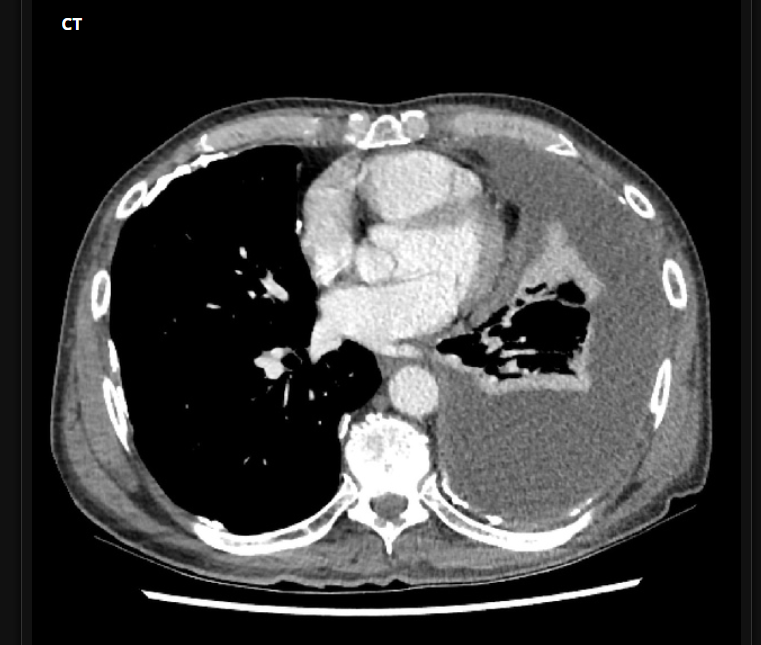

2 anos, masculino

Cisto de duplicação esofágico

Predleção por meninos; diagnosticados na infância

Em geral assintomáticos; podem provocar estridor

Mais comuns no esôfago distal; geralmente não comunicam com a luz do esôfago;

TC: Cisto com densidade de líquido, margens bem definidas que podem realçar com contraste; podem complicar com hemorragia, infecção: nível liquido, espessamento parietal.